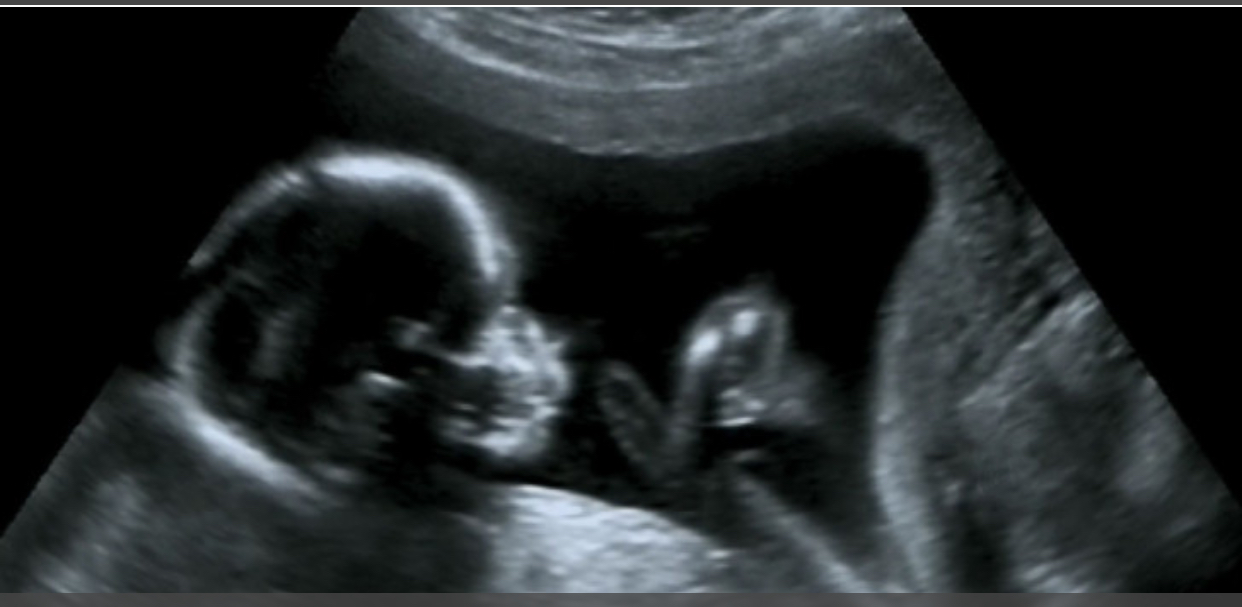

كشف باحثون من جامعة فيرارا الإيطالية، في دراسة نشرت بمجلة PLOS One، أن الأجنة الذين يكثرون من التثاؤب بين الأسبوعين 23 و31 من الحمل قد يكونون أكثر عرضة لولادة بأوزان أقل نسبيا. واعتمدت الدراسة على مراقبة 32 جنينا بصحة جيدة عبر التصوير بالموجات فوق الصوتية لمدة 22.5 دقيقة لكل جنين، وسجلت معدلات تثاؤب تراوحت بين صفر وست مرات خلال فترة الرصد، بمتوسط 3.6 مرات في الساعة.

ويعرف التثاؤب بأنه سلوك شائع لدى الفقاريات، إلا أن وظيفته الدقيقة عند الإنسان ما زالت غامضة. ويبدأ الجنين بالتثاؤب منذ الأسبوع الحادي عشر من الحمل، حيث يقوم بفتح فمه وحركات تشبه الشهيق والزفير، رغم عدم وجود هواء يتنفسه.